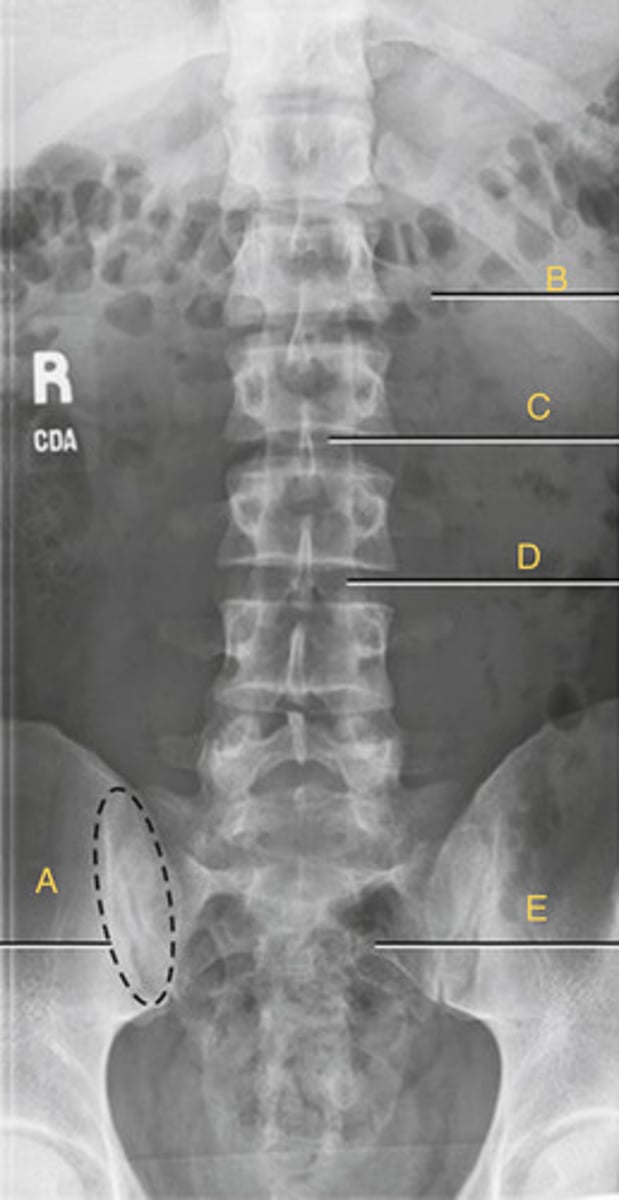

L2 body

A.

L3 transverse process

B.

L3-4 zygapophyseal joint

C.

L5, superior articular process

D.

L3 Pedicle

E.

L4 pars interarticularis

F.

L4 inferior articular process

G.

What position?

Oblique lumbar